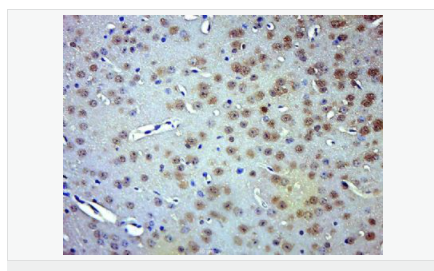

交叉反應(yīng):Human,Mouse,Rat(predicted:Dog,Pig,Cow,Horse,Sheep) 推薦應(yīng)用:WB,IHC-P,IHC-F,ICC,IF,Flow-Cyt,ELISA

產(chǎn)品應(yīng)用WB=1:500-2000 ELISA=1:5000-10000 IHC-P=1:100-500 IHC-F=1:100-500 Flow-Cyt=1ug/Test ICC=1:100 IF=1:100-500 (石蠟切片需做抗原修復(fù))